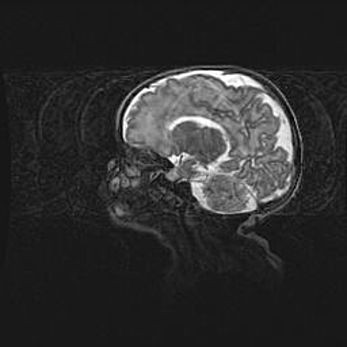

Подострая гематома правой гемисферы мозжечка.

Наружная гидроцефалия.

Возраст: 15 дней

Вес: 3100 г

Пол: женский

Окружность головы: 37 см

Срок гестации: 35-36 недель

При открытой наружной форме гидроцефалии у новорожденных расширяются и переполняются субарахноидные пространства.

Кровоизлияния в мозжечок имеют две клинико-анатомические формы: полушарные гематомы и кровоизлияния в червь.

К появлению этой патологии может привести: повреждения головного мозга, возникающие в результате асфиксии и гипоксии плода при беременности, или травмы во время родов. Редко гематома мозжечка может быть результатом первичной коагулопатии и сосудистой мальформации, диссеминированном внутрисосудистом свертывании, изоиммунной тромбоцитопении.